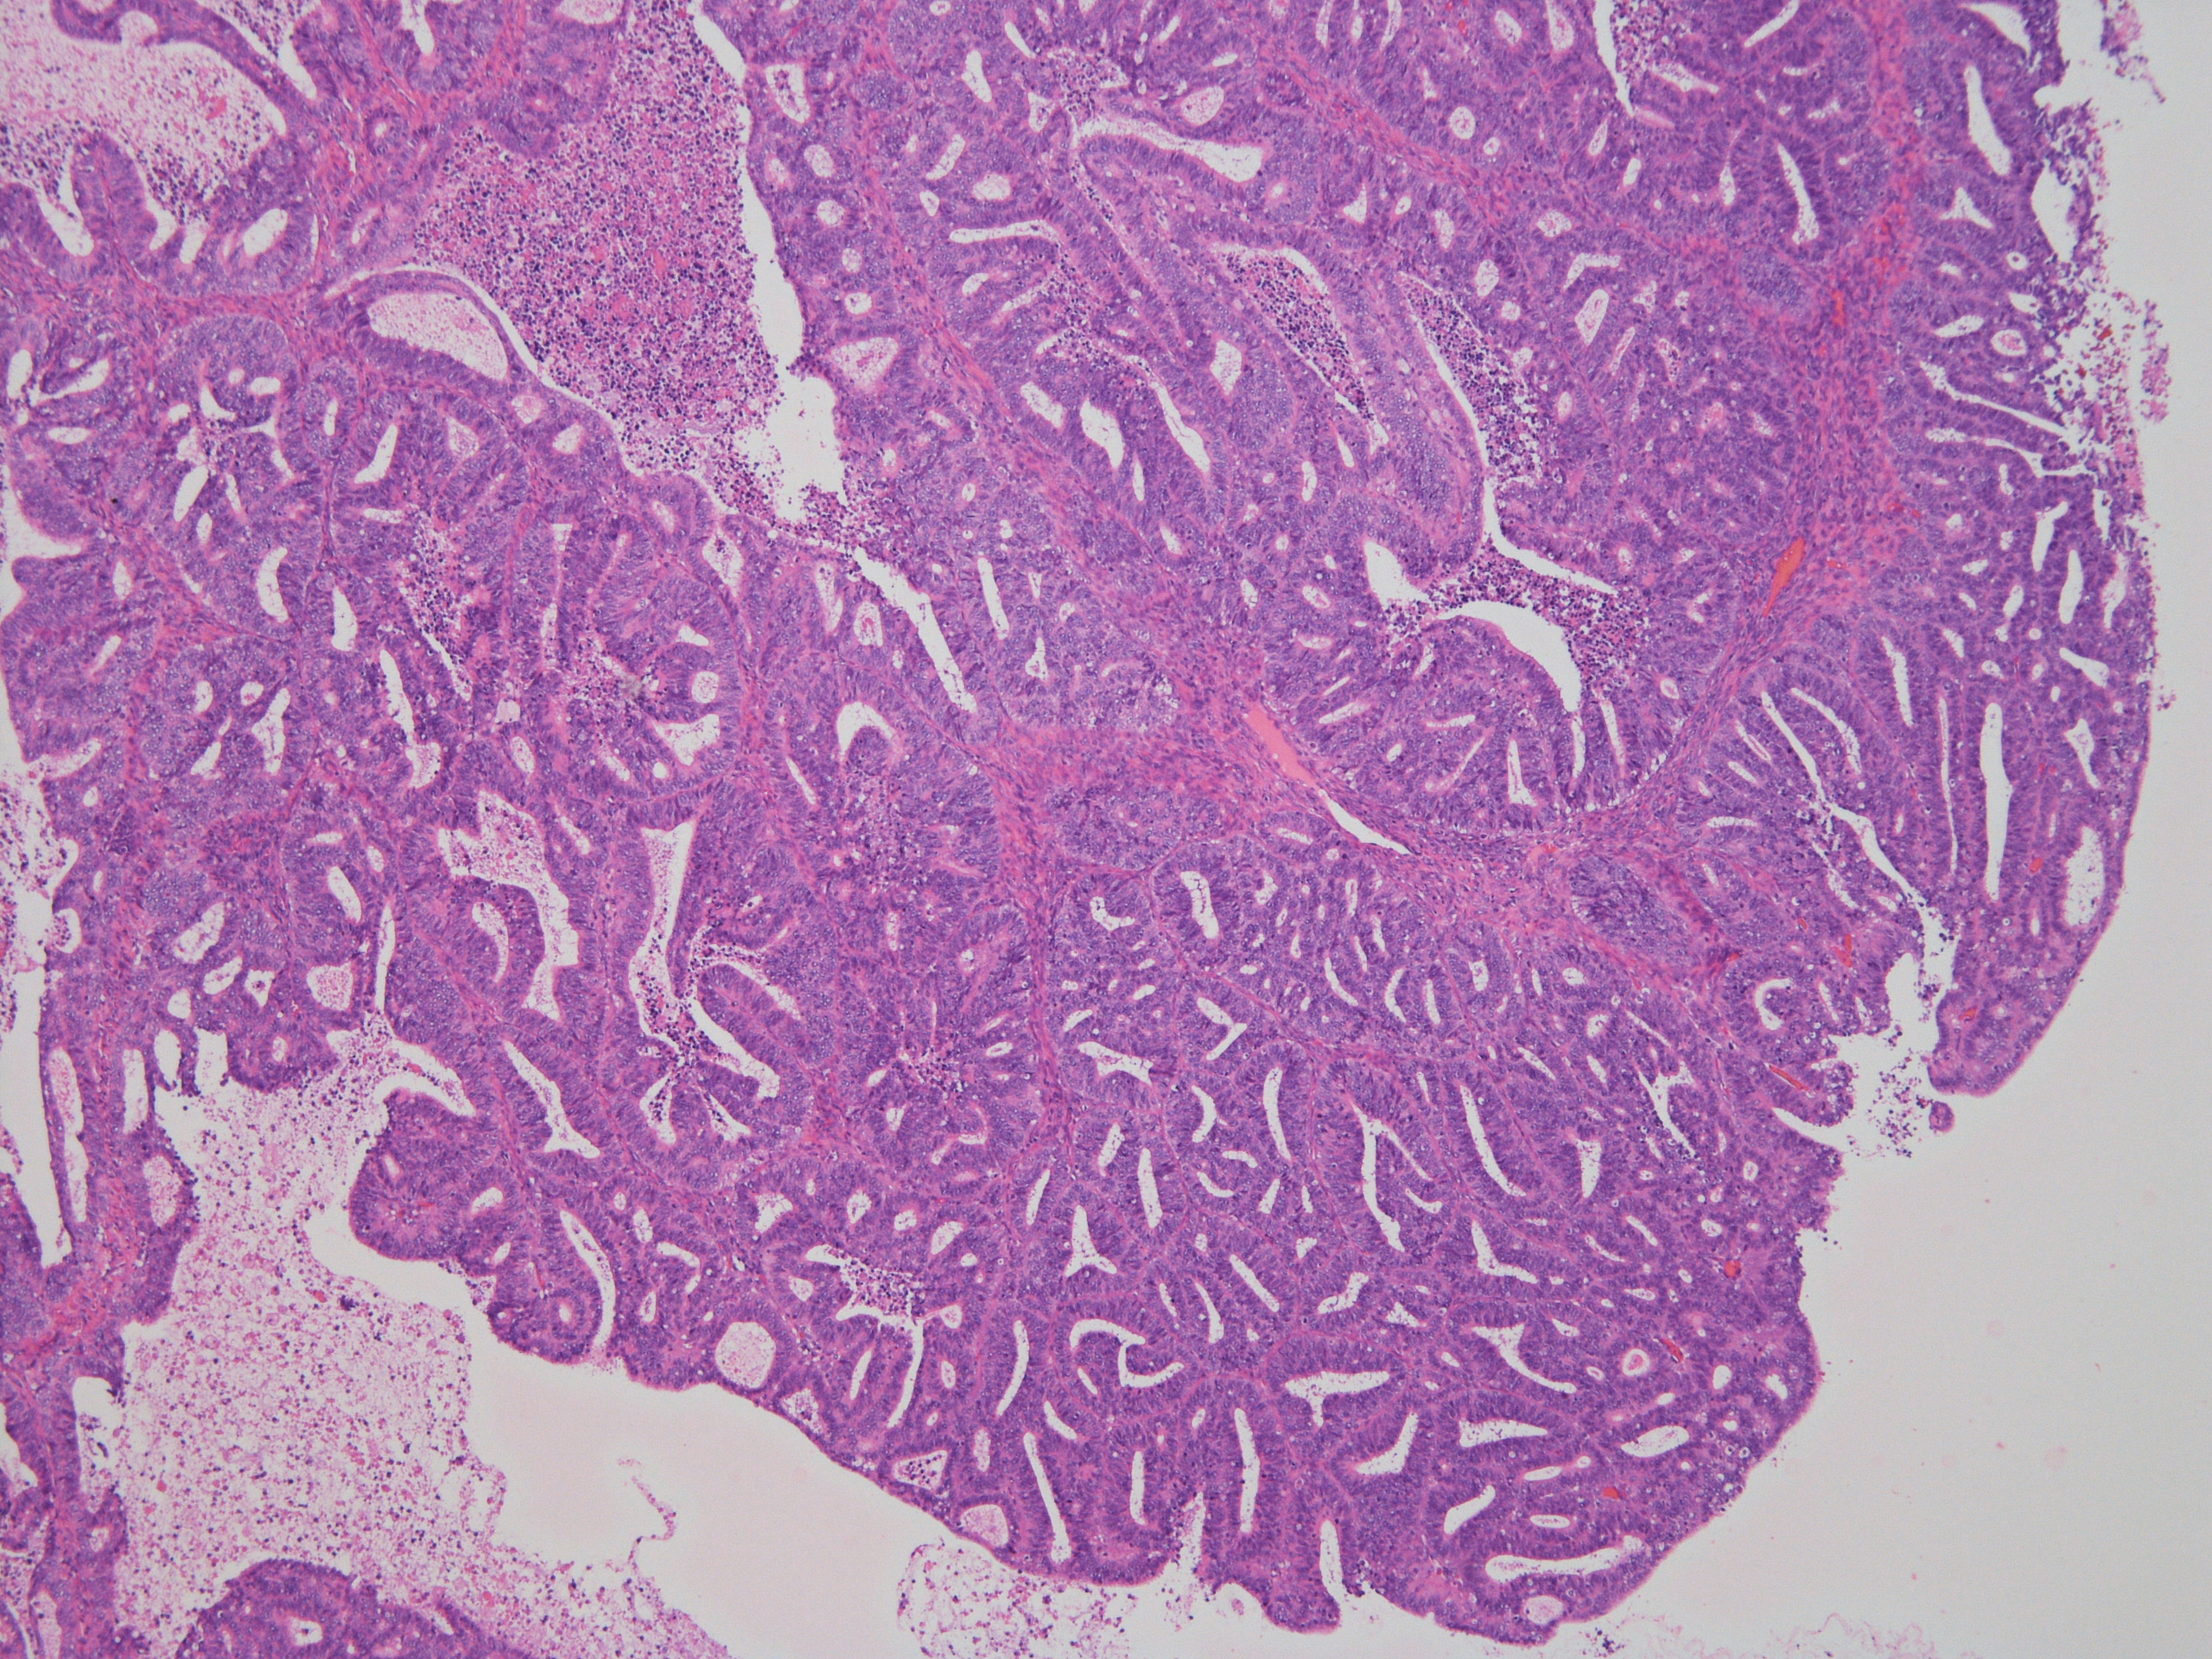

症例1解答、解説、討論記録

解答:類内膜癌(Grade1)

土管状集塊やシート集塊、大型組織様集塊、間質細胞集塊が出現している中に、不整突出集塊をわずかに認めた。

細胞診は、不整形突出集塊が単層で核異型に乏しいため「陰性」と判定したが、

手術標本(子宮摘出)の病理診断は類内膜癌(Grade1)で、手術標本と細胞診の所見に乖離を認めた。

渡辺先生より、細胞診の不整形突集塊は「手術標本で子宮内膜増殖症の所見も認められたので子宮内膜増殖症を見ている可能性がある」

とコメントを頂いた。